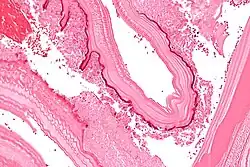

Larval/hydatid cyst stage

From the embryo released from an egg develops a hydatid cyst, which grows to about 5–10 cm within the first year and can survive within organs for years.[25] Cysts sometimes grow to be so large that by the end of several years or even decades, they can contain several liters of fluid. Once a cyst has reached a diameter of 1 cm, its wall differentiates into a thick outer, non-cellular membrane, which covers the thin germinal epithelium. From this epithelium, cells begin to grow within the cyst. These cells then become vacuolated and are known as brood capsules, which are the parts of the parasite from which protoscolices bud. Often, daughter cysts also form within cysts.[24]